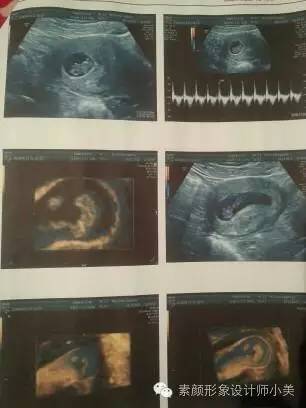

9周胎儿发育

进入第9周,你的胚胎从现在开始可以称为“胎儿”了,也可以称之为“小宝宝”。为了接纳新居民,你的子宫膨胀得非常大,现在胎儿的尺寸大约有25毫米,而且胎儿许多位置都有所改变,如胚胎期的小尾巴不见了等。现在所有的器官、肌肉、神经开始工作。手部从手腕开始变得稍微有些弯曲,双脚开始摆脱蹼状的外表,眼帘开始覆盖住眼睛。